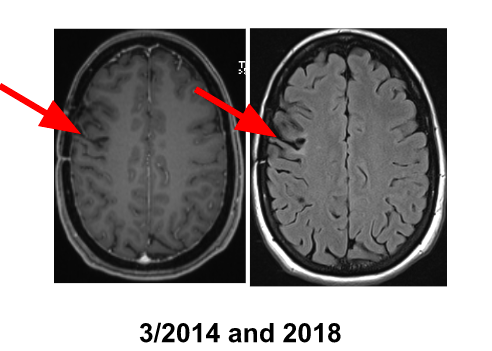

Alpha therapy in low grade gliomas (WHO II), 19 years of experience! 12-years recurrence free survival in diffusive low grade astrocytoma II in young woman, no other therapies

hypodense area with enhancing rim (T1)

transient perifocal edema reaction (T2)

Beginn day 9, resolved day 40 after alpha-therapy: Moderate brachiofacial hemiparesis L, completely resolved, No permanent deficit!

8 years stable course (2011-2019)

No open surgery

2 years recurrence-free survival in a now 40-year old diffusive infiltrative astrocytoma grade II patient, no functional deficit, ±“clean“ MRI